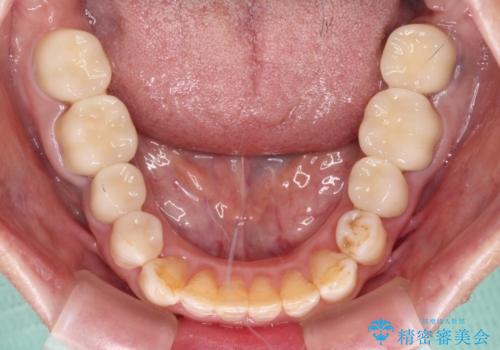

- 全顎的な歯列不正と、銀歯だらけの奥歯を気にして来院された患者様です。

奥歯の銀歯は、セラミッククラウンを装着するには歯の高さが不十分であり、そのままでは矯正治療を行うことが困難であるため、歯冠長延長術を行うこととしました。

また、根管治療の必要な歯がいくつかあるため、歯周外科治療の治癒期間を利用して根管治療を行い、その後インビザラインにて矯正治療を行うこととしました。

矯正治療後にはオールセラミッククラウンにて補綴治療を行うこととしました。

歯冠長延長術を行ったことで、自然な形態かつ清掃性の高いセラミッククラウンを装着することができました。

全顎的に治療を行ったため、治療期間も費用も負担は大きくなりましたが、統一感のある仕上がりとなりました。